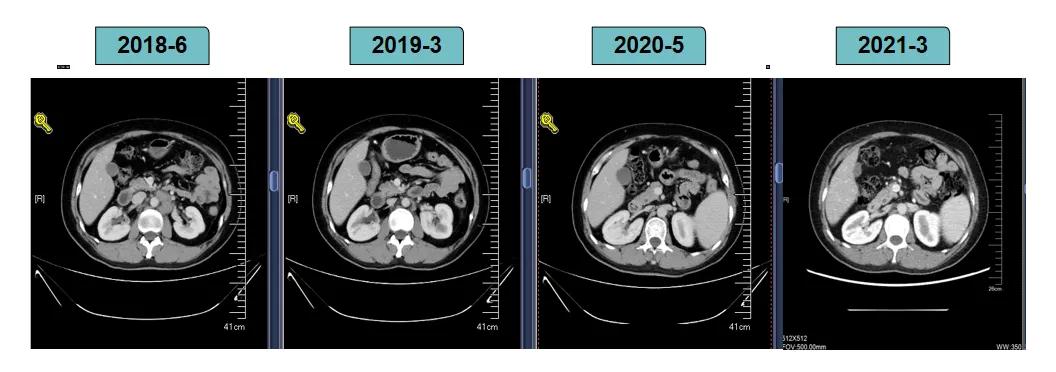

胸腹部增强CT示(2018-6-28):胸骨后占位,肝内异常强化灶,腹膜后肿大淋巴结。

靶病灶:腹主动脉左侧和下腔静脉右侧淋巴结

非靶病灶:肝左叶、肝右前叶下段;纵膈胸骨后淋巴结节;前上纵膈淋巴结;腹膜后小淋巴结

影像学评估-纵膈淋巴结:

影像学评估-肝脏:

影像学评估-腹膜后淋巴结: